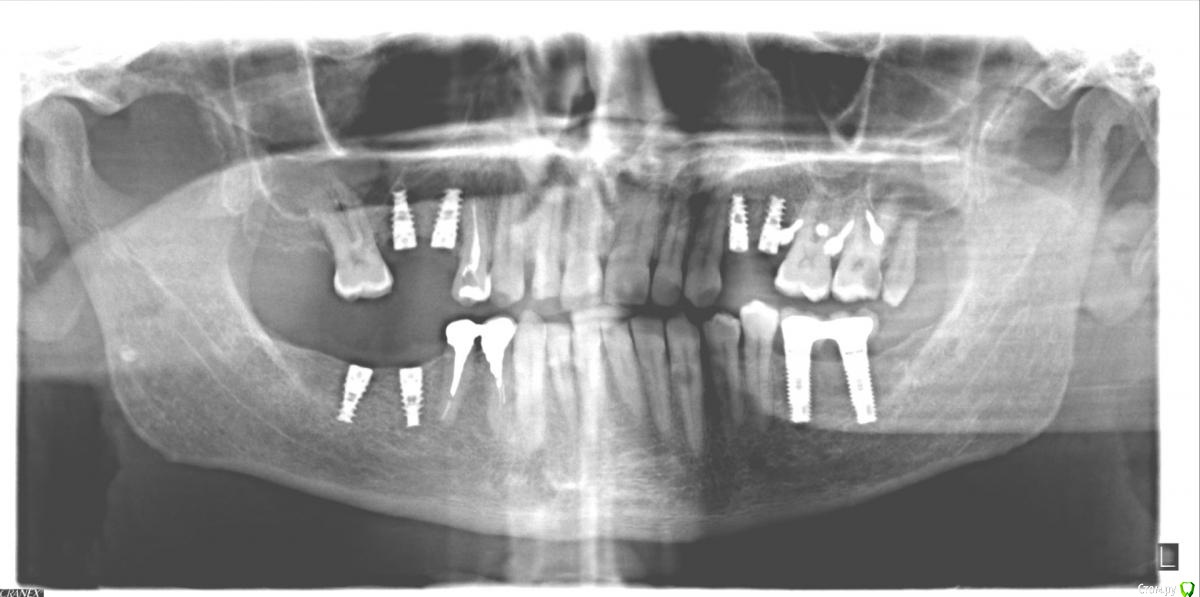

LK9722 Опубликовано 20 февраля, 2015 Автор Поделиться Опубликовано 20 февраля, 2015 фото после лечения верхней 4-ки и имплантов сверху Ссылка на комментарий

shishok Опубликовано 22 февраля, 2015 Поделиться Опубликовано 22 февраля, 2015 1)кариес на 27 зубе начался на задне-пришеечной поверхности(не сверху).Его видно на втором панорамном снимке.26 зуб рентгенологических признаков кариеса не имеет.2)восьмой удалить!3)по рг-снимку кариеса на 16 зубе нет,но нужно смотреть очно.4)по имплантам не подскажуя.т.к. я-терапевт.5)если 14 зуб беспокоит,то лучше перелечить.6)а 46 зуб нужно было удалять давним-давно(судя по первой ОПТГ).Вопрос о сроке службы моста на данный момент уже чисто риторический Ссылка на комментарий